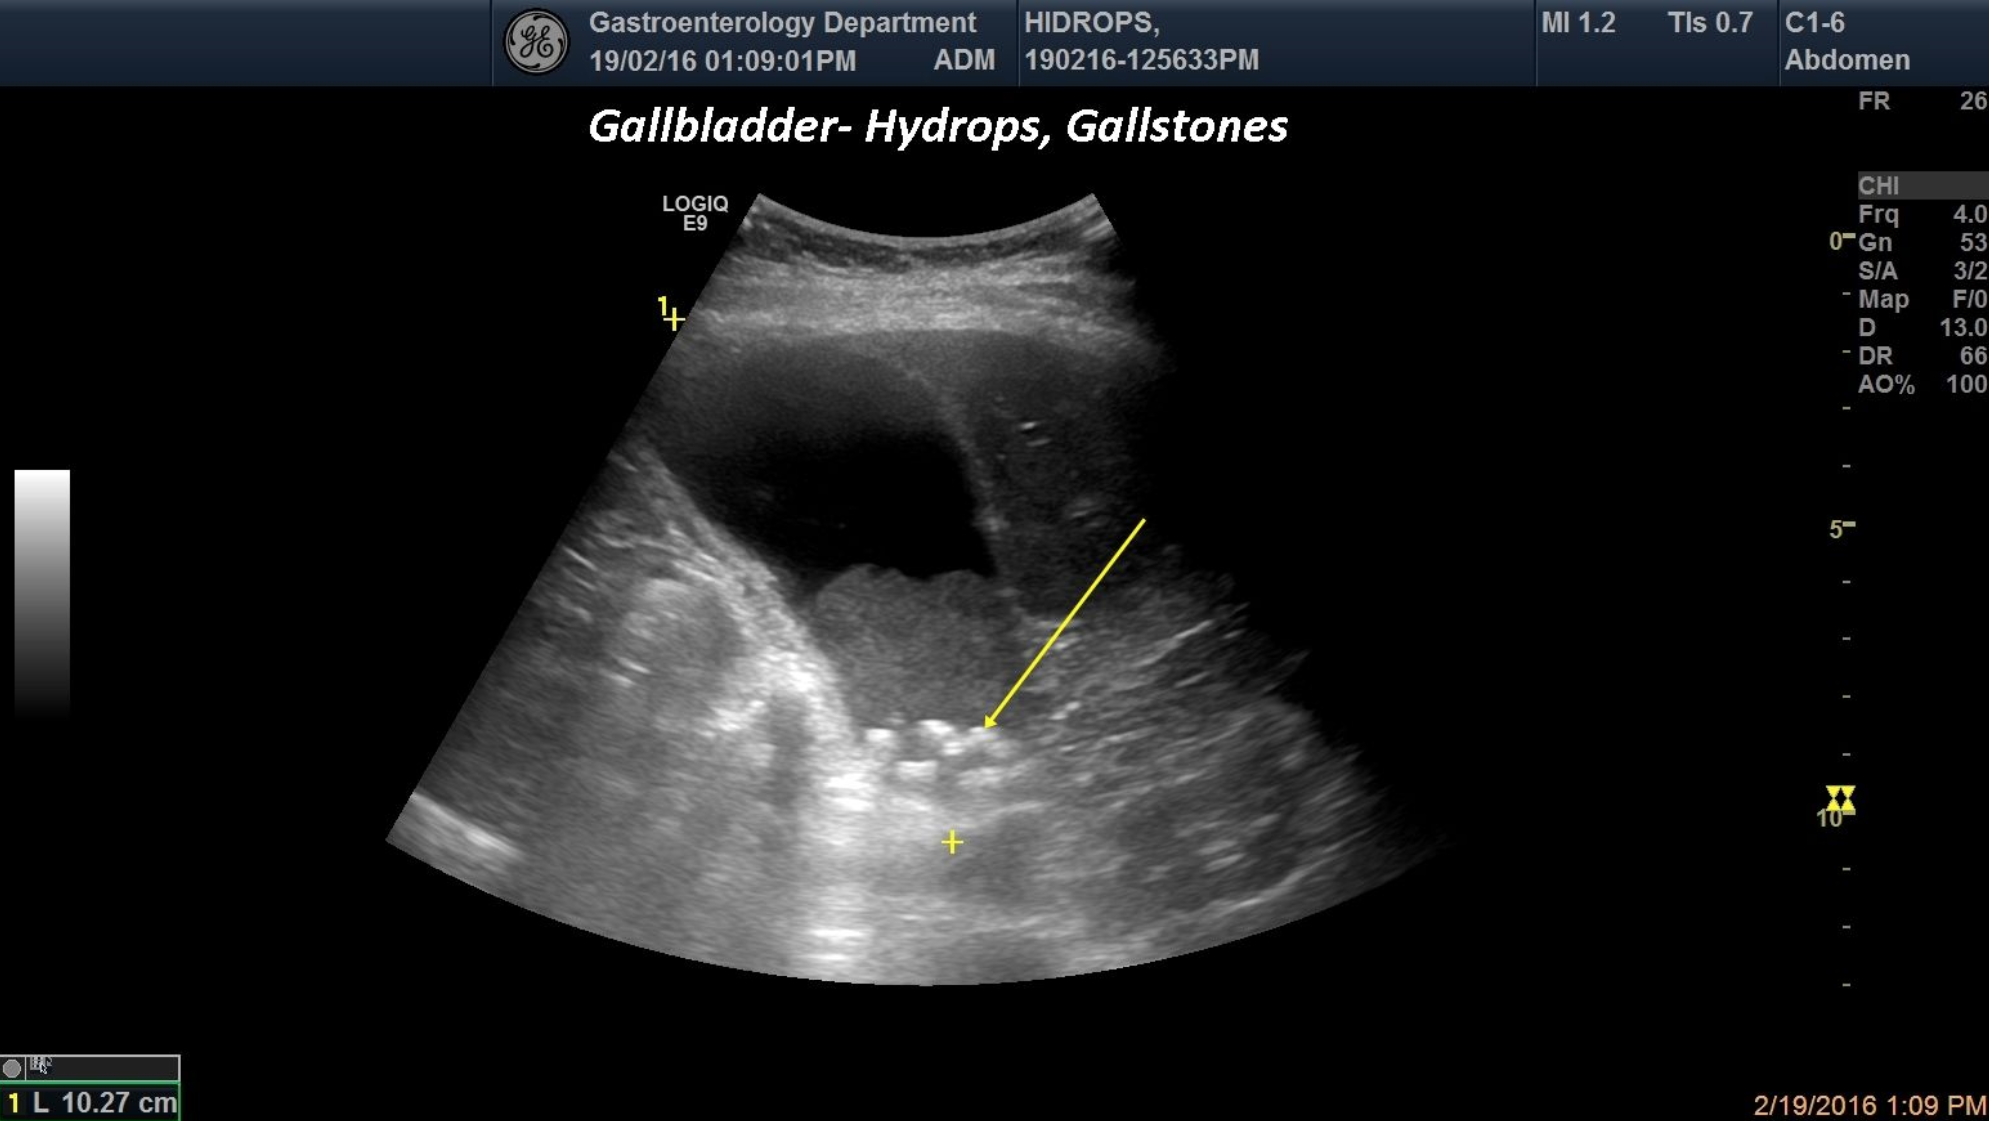

TITLE: Gallbladder Hydrops, Gallstones and sludge

A 59-year-oldpatient was brought into the emergency room for right upper quadrant pain that started after a rich meal. Distended gallbladder,multiple infundibular gallstones and biliary sludge were depicted in standard ultrasound.

Gallbladder hydrops, gallstones, biliary sludge